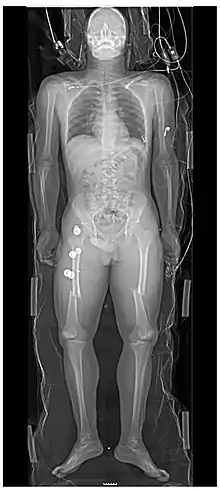

Persons with major trauma commonly have chest and pelvic x-rays taken,[6] and, depending on the mechanism of injury and presentation, a focused assessment with sonography for trauma (FAST) exam to check for internal bleeding. For those with relatively stable blood pressure, heart rate, and sufficient oxygenation, CT scans are useful.[6][25] Full-body CT scans, known as pan-scans, improve the survival rate of those who have suffered major trauma.[26][27] These scans use intravenous injections for the radiocontrast agent, but not oral administration.[28] There are concerns that intravenous contrast administration in trauma situations without confirming adequate renal function may cause damage to kidneys, but this does not appear to be significant.[25]

In the U.S., CT or MRI scans are performed on 15% of those with trauma in emergency departments.[29] Where blood pressure is low or the heart rate is increased—likely from bleeding in the abdomen—immediate surgery bypassing a CT scan is recommended.[30] Modern 64-slice CT scans are able to rule out, with a high degree of accuracy, significant injuries to the neck following blunt trauma.[31]